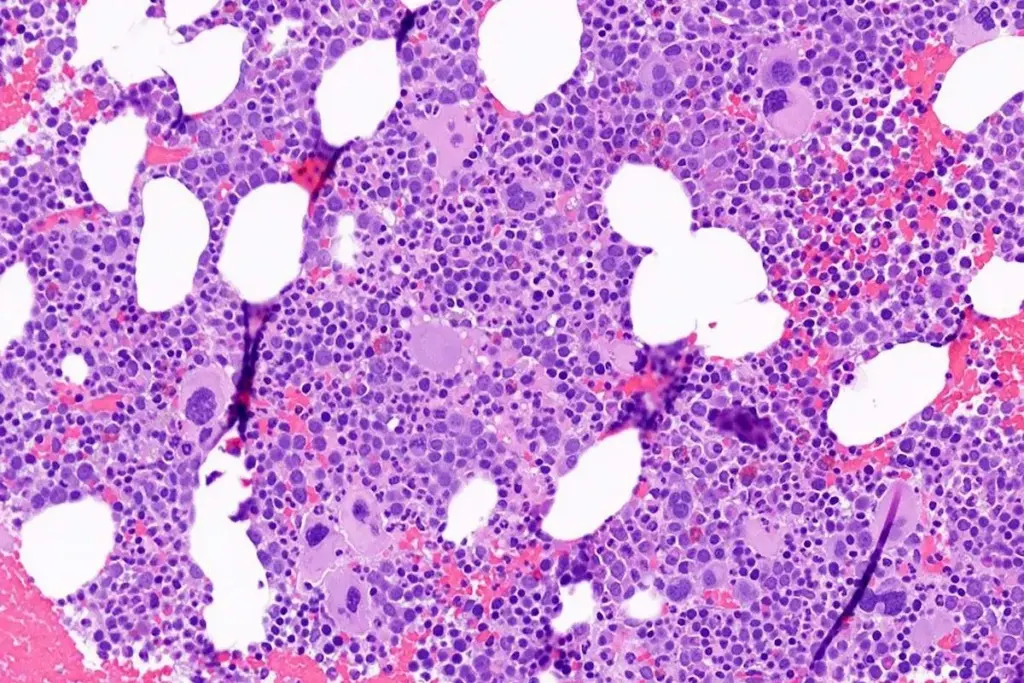

Bone Marrow Biopsy and Aspiration

After the CBC, a bone marrow biopsy and aspiration are done. These tests check the bone marrow’s cell count and shape. A sample is taken from the hipbone or sternum.

Bone Marrow Test Findings: In aplastic anemia, the bone marrow looks very low in cells. The aspiration shows fewer blood-making cells and more fat cells.